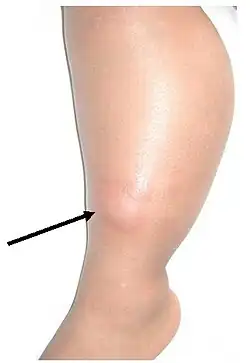

Beim Tuberkulin-Hauttest (auch Mendel-Mantoux-Test genannt) wird eine definierte Menge gereinigter und filtrierter Antigene aus Mykobakterien (Tuberkulin) in die Oberhaut (Epidermis) gespritzt. Ebenfalls gebräuchliche Stempeltests sind sehr unzuverlässig und daher nicht empfehlenswert. Hat das Immunsystem des getesteten Menschen schon einmal Kontakt mit Mykobakterien gehabt, tritt an der entsprechenden Stelle innerhalb von drei Tagen eine Abwehrreaktion mit Einwanderung von Abwehrzellen in die Haut ein, die zu einer Verdickung führt. Es handelt sich hier um eine Typ IV Reaktion (nach COOMBS). Bereits sechs Wochen nach einer Infektion mit TBC wird der Test positiv.

Eine tastbare Verhärtung an der Teststelle bezeichnet man als positive Reaktion. Dies kann bedeuten, dass eine Tuberkulose-Infektion stattgefunden hat. Über eine Erkrankung sagt der Test allerdings nichts aus. Auch nach einer Tuberkulose-Schutzimpfung ist eine positive Testreaktion möglich. Bleibt die Haut an der Teststelle unverändert oder zeigt sich nur eine Rötung, wird dies als negativ bewertet. Eine Tuberkulose-Infektion ist dann mit hoher Wahrscheinlichkeit ausgeschlossen.